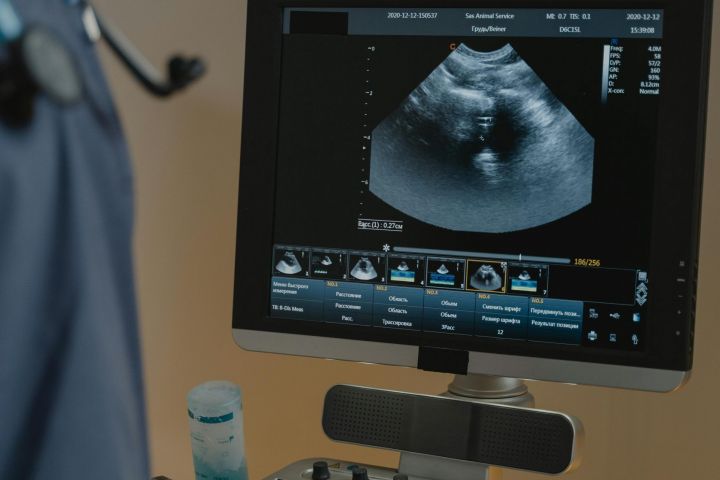

Infiltrations guidées par imagerie

Échographie, bras en C et scanner

Pour un traitement précis et sécurisé, nous réalisons des infiltrations antidouleur sous guidage échographique ou radiologique (bras en C), notamment au niveau des articulations vertébrales, des racines nerveuses ou des tendons profonds. Cela permet une administration ciblée du traitement et de meilleurs résultats.

Diagnostic orthopédique par échographie

Nous utilisons l’échographie pour examiner les tendons, ligaments, muscles et articulations en temps réel, permettant de détecter les déchirures, inflammations ou accumulations de liquide sans rayonnement.